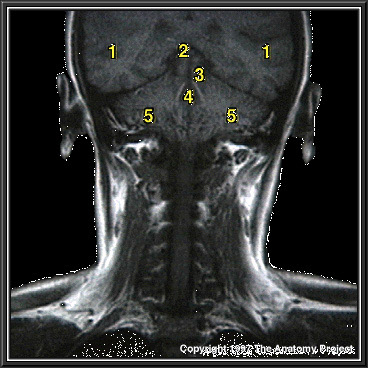

N2A7P10

803